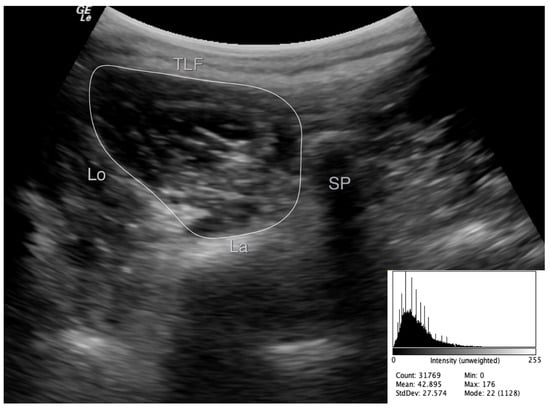

2.4. Images Assessment